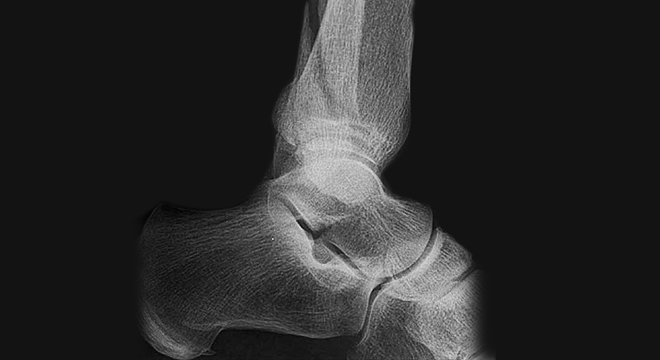

Knöchelbruch: Röntgenbild des Sprunggelenks

• Röntgenbild in 2 Ebenen, evtl. auch des ganzen Unterschenkels, da das Wadenbein auch relativ weit oben gebrochen sein kann

• Bei komplexen Brüchen evtl. Computertomographie zur besseren Operationsvorbereitung